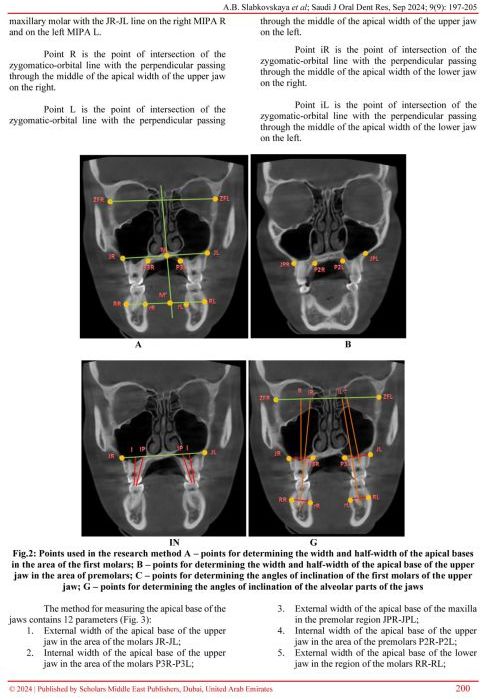

В сентябре вышла статья на английском языке под названием A Method for Studying the Size and Position of the Apical Bases of the Jaws Using Computed Tomography of the Jaws в которой профессор Севан Мухамед Насер и врач ортодонт Севан Сюзанна Мухаммедовна выступили в роли соавторов.